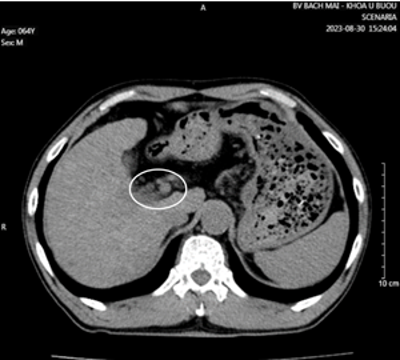

Cắt lớp vi tính ổ bụng có tiêm thuốc cản quang:

Hình 4: Theo dõi di căn hạch rốn gan (vòng tròn trắng).